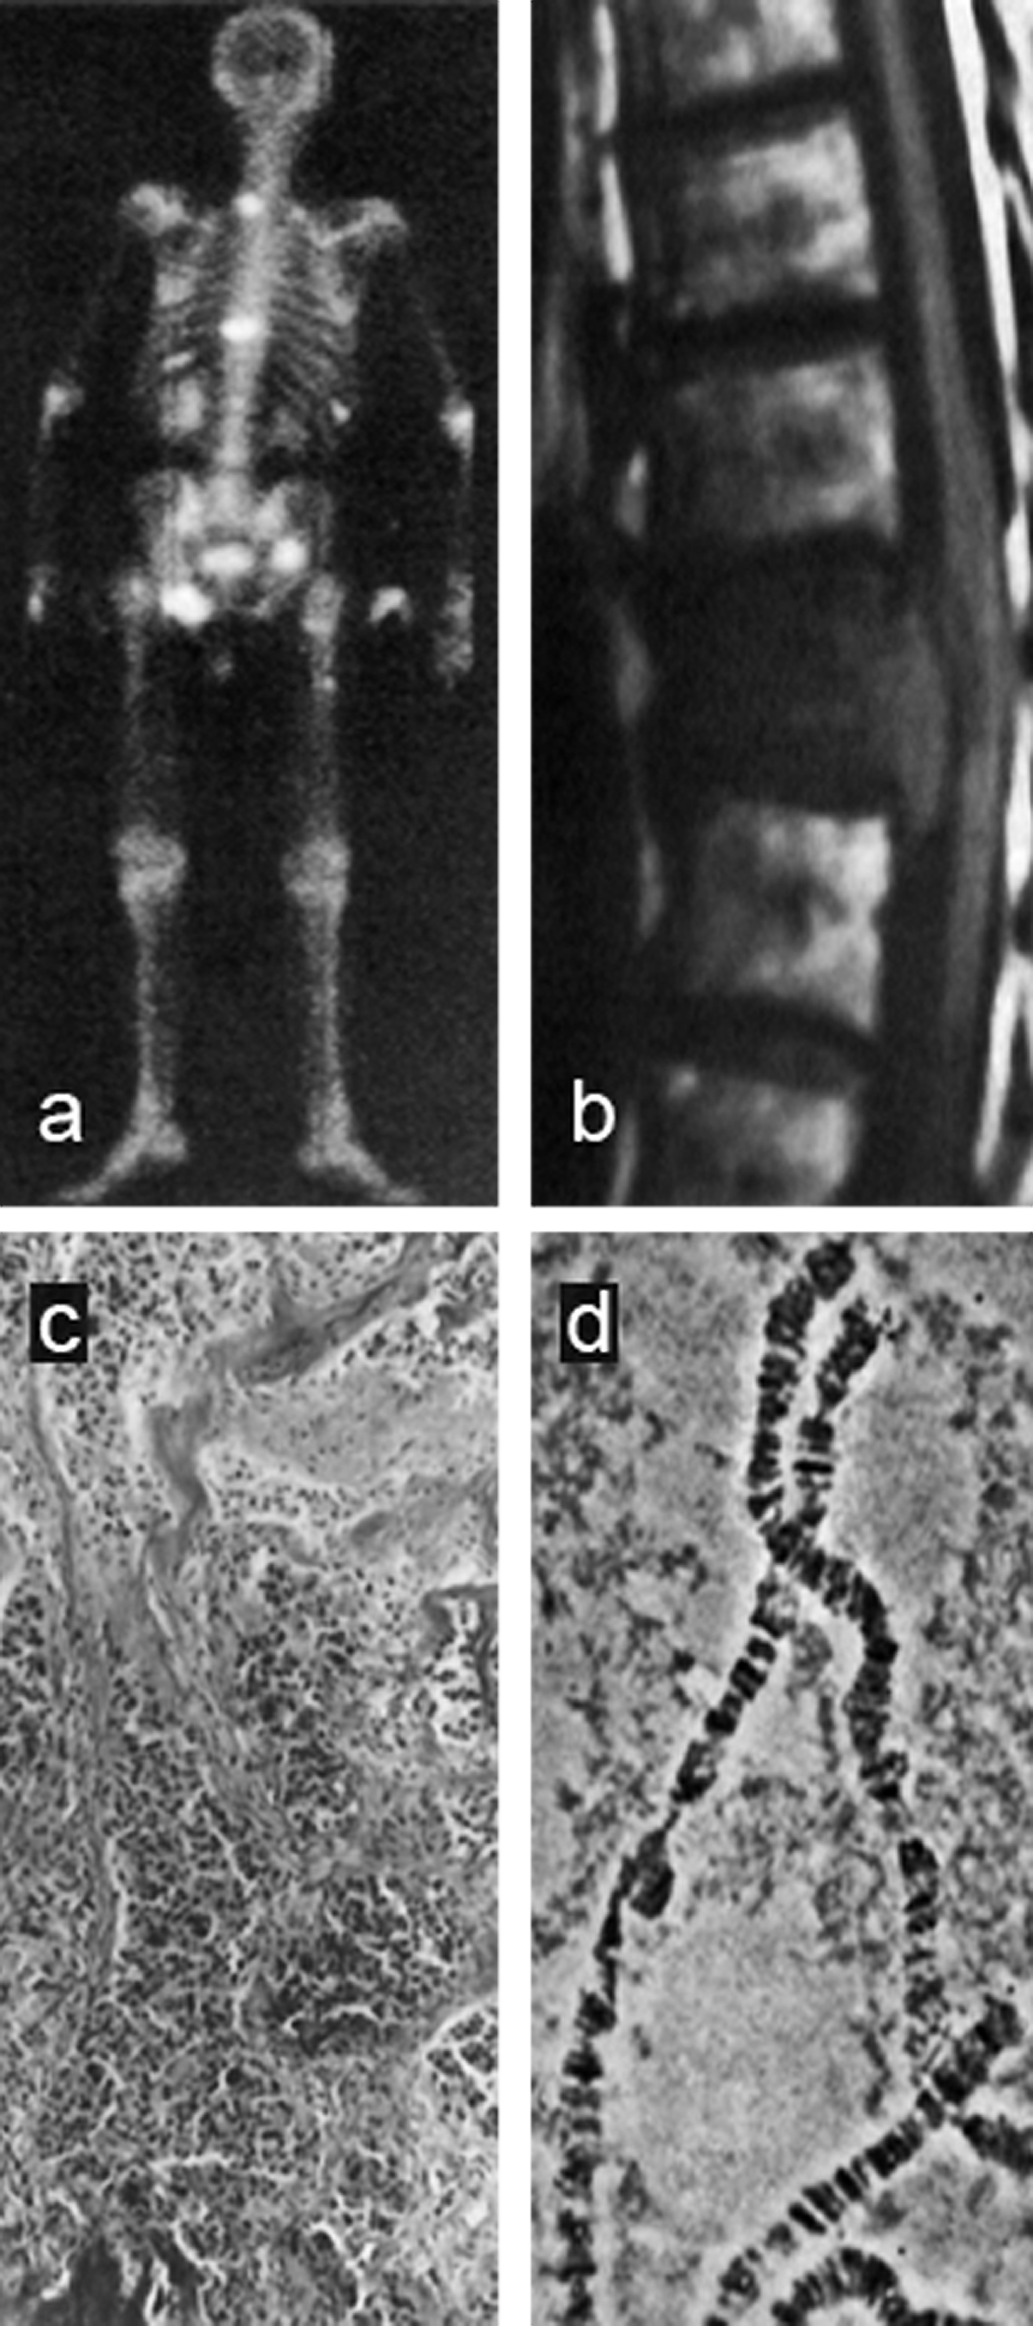

Given the increasing understanding of molecular mechanisms of disease and the de­ve­lop­ment of in­no­va­tive therapies at the genetic level, molecular imaging is aimed at the exploitation of specific molecules as the source of image contrast (Figure 13-20). However, although MR imaging does not possess sufficient sensitivity to image single molecules, responsive MR agents can dynamically change one or more of their physico-chemical properties when interacting with their intended molecular biomarker.

Figura 13-20:

(a) Whole body screening: radioisotope scan;

(b) organ level: MR spine study without con­trast enhancement;

(c) tissue level: bone histology;

(d) genetic level: chromosome screening.